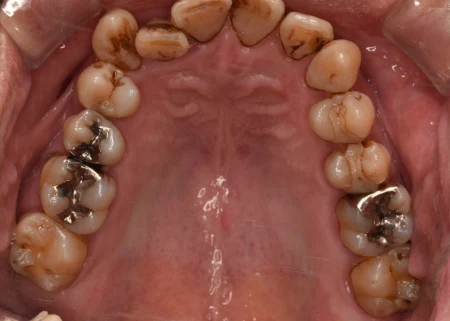

一般歯科 2023.0450代男性「着色を落として、詰め物もやり直したい」歯周病治療と専用機械による着色除去を並行し、歯と歯肉の状態を改善して詰め物をやり直す準備ができた症例